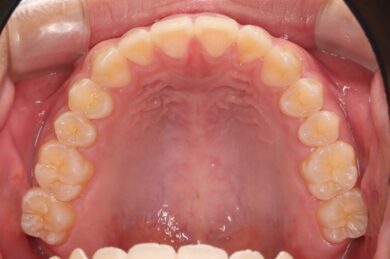

初めにマウスピース矯正「インビザライン」による術前矯正を11か月行いました。各隙間を寄せ、インプラントを埋入するスペースを確保し、適切な咬合関係を確立します。

インビザラインの治療計画では、下顎前歯がより美しく審美的に並ぶよう、ご自身の歯とインプラントの歯がほぼ同じ幅径になるよう計算し配列を行いました。

下顎の前歯は通常6本ですが、中央から2番目の歯(側切歯)が左右2本とも欠損している先天性欠如の患者様です。